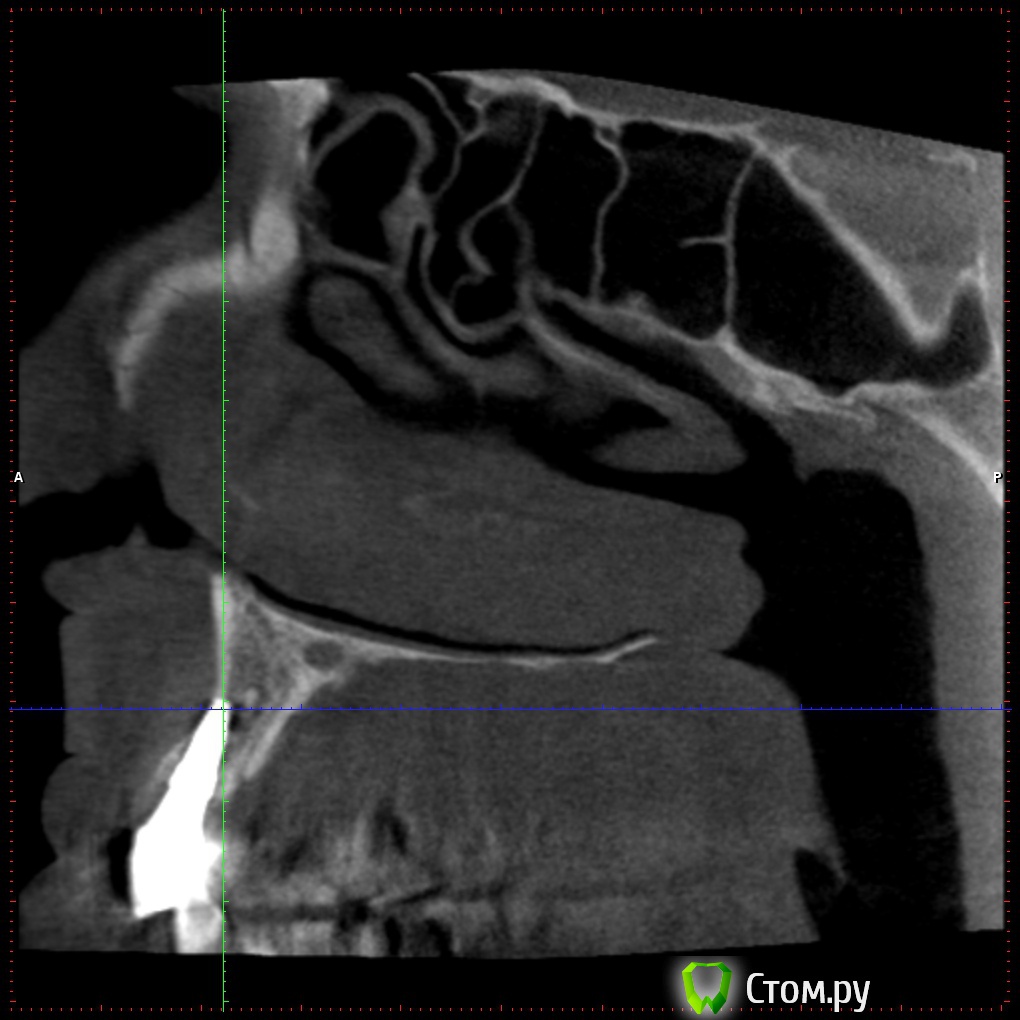

Britanez Опубликовано 2 июня, 2014 Поделиться Опубликовано 2 июня, 2014 В июле 2013 года были установлены 2 импланта 2 и 6 , 6ка с открытым синус лифтингом, в феврале 2014 установили коронки. Две недели назад обратил внимание на воспаление десны над обеими коронками,появился свищ над вторым имплатом и выделения белого цвета.Обратился к врачу, назначили пропить антибиотики 5 дней и сделать КТ. Антибиотики пропил над 6кой воспаление прошло ,над 2кой осталось,по результату КТ сказали что ушла кость и 2ку скорее всего придется удалять.Подскажите что можно сделать в данной ситуации, можно ли сохранить имплант?Ссылка на кт: http://my-files.ru/vbs51uСделал срезы кт: Ссылка на комментарий

Britanez Опубликовано 9 июня, 2014 Автор Поделиться Опубликовано 9 июня, 2014 Извините, что пишу в Вашей теме, просто хочу выразить сочувствие. Напишите потом, пожалуйста, как пойдут Ваши дела дальше, и что говорят врачи, почему произошло отторжение? А синус делали одновременно с постановкой обоих имплантов?? И ещё, выскажу просто мнение для администрации сайта и стоматологов, хотя сообщение наверняка удалят. Меня удивляет, для чего тогда сделана ветка для вопросов пациентов, когда за несколько дней ни один уважаемый стоматолог не заглянул и ничего не написал... После этого задумаешься, стоит ли размещать свои снимки, фотографии и проблемы..... Отвечу здесь если кому то интересно.Синус на 6ку делали одновременно с постановкой двух имплантов.Врачи говорят, что воспаление пошло из-за того что верхний край импланта вышел за пределы костной ткани (на втором снимке видно) и при нагрузке началось воспаление, хотя имплант стоял очень крепко ,открутить не смогли, выпиливали, чем то типа круглой коронки.Если здесь кто нибудь из врачей объяснил (подтвердил) причину воспаления, был бы очень признателен. Ссылка на комментарий

Bier Опубликовано 9 июня, 2014 Поделиться Опубликовано 9 июня, 2014 Имплантат частично стоял не в кости и кости судя по в ему было очень мало еще до имплантации. Ссылка на комментарий